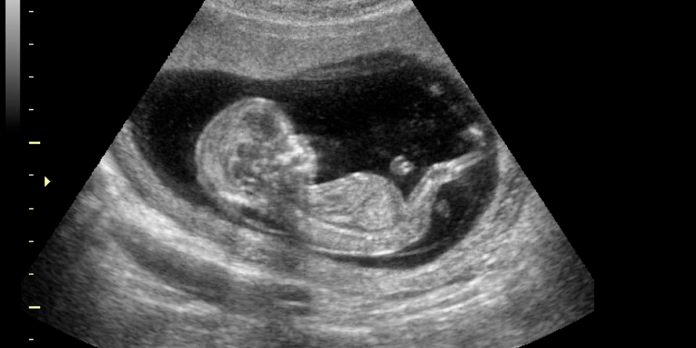

El fetus in fetu es una condición extremadamente rara en la que un gemelo se desarrolla dentro del cuerpo de su hermano en lugar de hacerlo de manera independiente en el útero materno. En el caso de Itzamara, un examen ecográfico de rutina reveló que un feto ‘parásito‘ estaba creciendo en su abdomen, alimentándose del corazón y los nutrientes de su hermana.

Durante el embarazo de Mónica Vega, madre de Itzamara, el feto parásito carecía de placenta, corazón y cerebro, y dependía completamente del cuerpo de su hermana para sobrevivir. El cirujano Miguel Parra explicó que este tipo de fenómeno ocurre cuando el embrión destinado a formar gemelos no se divide en el momento adecuado. «Es uno de los casos más raros que vemos en medicina materno-fetal«, declaró el doctor Parra.